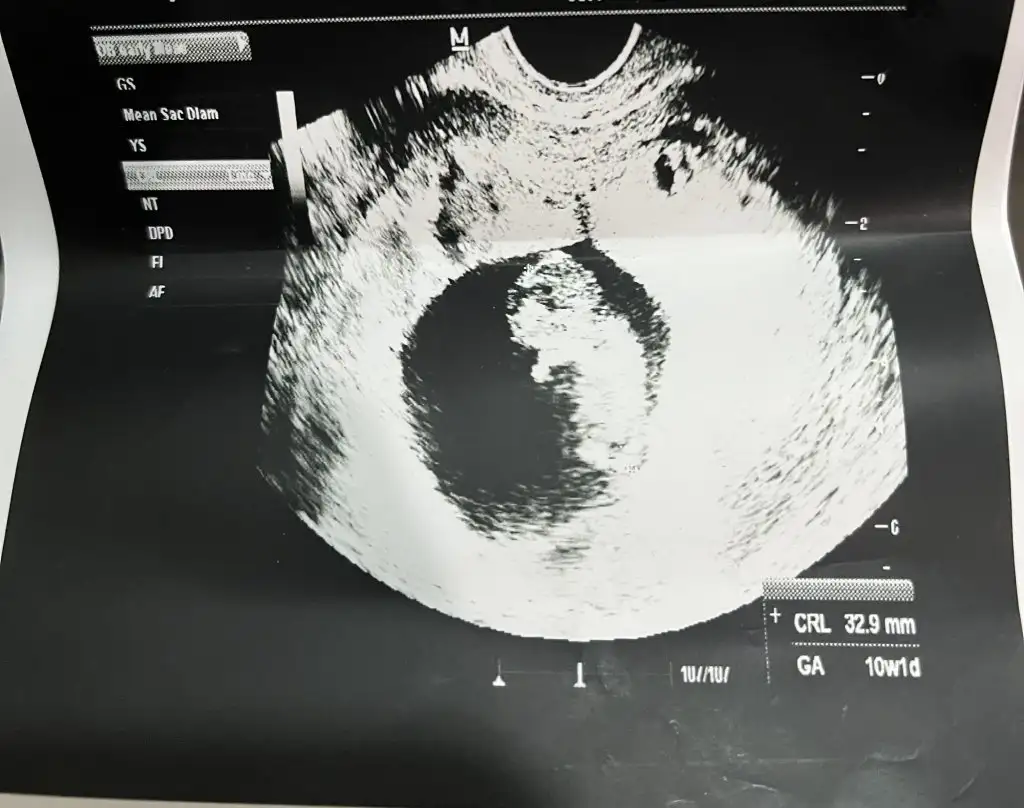

Benim 10+3 oldu galiba tam sayamadim da bulantım geçti ara ara hafif oluyor ama hiç rahatsız etmiyor ve iki gündür kasıkta hafif batmalar oluyor böyle kasikla beraber tüm göbeğim sanki kas ağrısı varmış gibi ağrıyor sordum arkadaşlara rahim buyumesinden oluyormuş bu ama aranızda bulantısı çabuk geçen varmı benim iki gündür çok iştahım yok ama yemeklerden ve kokulardan rahatsız olmuyorum artıkKızlar sizde de kasık karın ağrısı var mı?

Bende cuma günü gittim 10+3 olmuşBenim 10+3 oldu galiba tam sayamadim da bulantım geçti ara ara hafif oluyor ama hiç rahatsız etmiyor ve iki gündür kasıkta hafif batmalar oluyor böyle kasikla beraber tüm göbeğim sanki kas ağrısı varmış gibi ağrıyor sordum arkadaşlara rahim buyumesinden oluyormuş bu ama aranızda bulantısı çabuk geçen varmı benim iki gündür çok iştahım yok ama yemeklerden ve kokulardan rahatsız olmuyorum artık